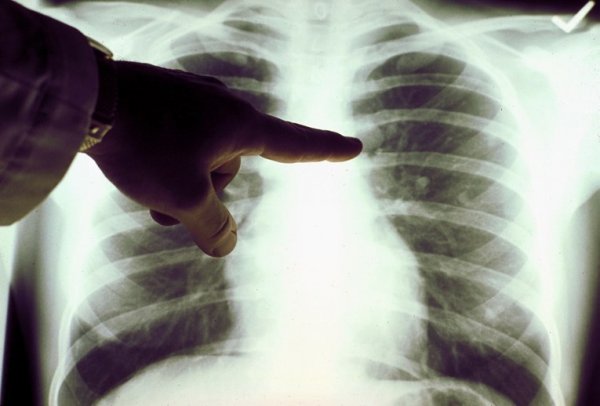

Ljubica Gašić iz Beograda očekivala je da će lako proći zakazanu kontrolu kod ljekara. Međutim, rezultati su bili poražavajući. Pronašli su joj rak pluća, u šezdeset petoj godini. Karcinom je zahvatio desno plućno krilo i ljekari su joj rekli da ne mogu da je operišu.

Ljubica, kao i većina pacijenata, nije imala nikakve simptome, a dijagnoza ju je dočekala kao grom iz vedra neba. Ostala je šokirana.

- Kod ljekara sam otišla samo da podignem lijekove za srce. Iskoristila sam to i požalila sam se na malaksalost, koju sam osjećala par dana ranije. Nakon prvog slušanja pluća, doktorki se nje dopalo šta čuje, zbog čega me je poslala kod specijaliste. Nakon desetak dana odlazim kod plućnog ljekara. Tada sam se već osjećala dobro i dok sam čekala da uđem u ordinaciju zapitala sam se šta ću ja ovdje. Ipak, snimak je pokazao da imam rak pluća, koji nije mogao da se operiše - priča Ljubica za "Blic".

U većini slučajeva, rak pluća ne daje nikakve simptome sve dok bolest već ne uznapreduje. Ipak, postoji i mnogo slučajeva u kojima ljudi simptome ove teške bolesti zamjenjuju nečim drugim, što je uvijek fatalna greška.

Zato je potrebno da što prije odete kod ljekara ako primjetite neke od ovih znakova, jer su u tom slučaju šanse za izliječenje značajno veće.